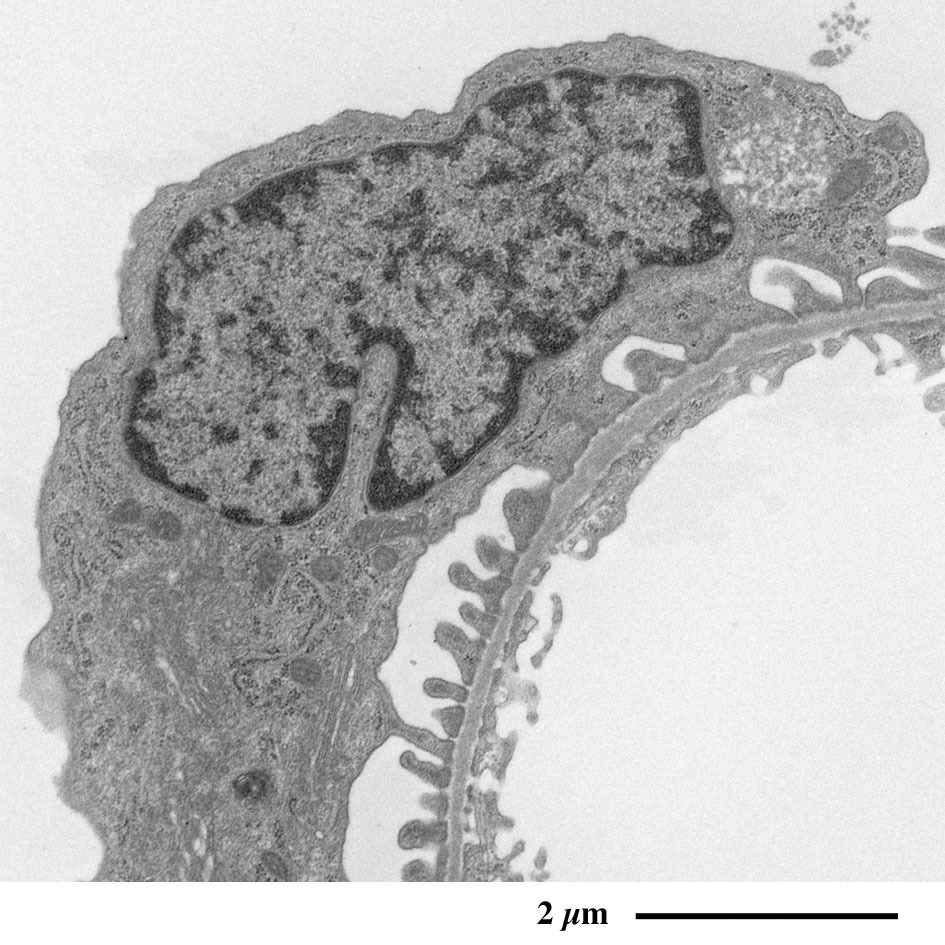

肾小球的电子显微镜图像

表面含有足细胞的毛细血管蟠曲穿行于肾小囊腔中,

其外周被肾小囊包裹。

毛细血管(红色)穿行于肾小囊腔内(绿色),其表面覆盖足细胞(肾小囊脏层),

整体被肾小囊(蓝色)壁层包裹。